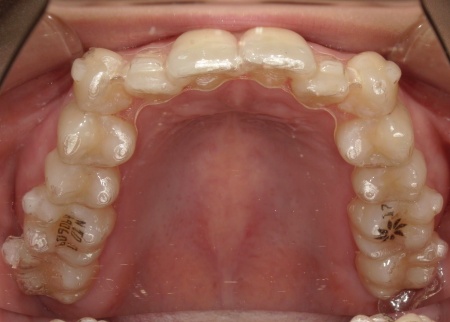

歯並びを改善する方法として、透明なマウスピースを段階的に交換しながら歯を動かしていくインビザラインコンプリヘンシブパッケージによる矯正治療を提案し、同意いただきました。

まず、患者様専用のマウスピースを作製し、1日一定時間装着していただくようご案内しました。

マウスピースは定期的に新しいものへ交換しながら、少しずつ歯を移動させています。

治療と並行して、歯と歯の間にスペースを作るためのIPRを適切なタイミングで実施しました。また、噛む力が強い傾向が見られたため、奥歯の噛み込みを抑え、歯をスムーズに動かすために「バイトランプ」と呼ばれる小さな突起をマウスピースの上の前歯の裏側に設置しています。